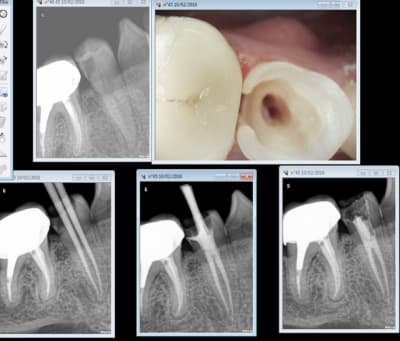

Voici un exemple de couplage microscope opératoire/cbct

RTE 36 en octobre2012 ;3 heures de RTE pour recherche de canaux sous micro inserts ultrasons/il y avait une LIPOE

digue+hypo+système R-endo microméga instruments à mains

vérification au CBCT en 2016

disparition des LIPOE

ici on obtient une guérison apicale